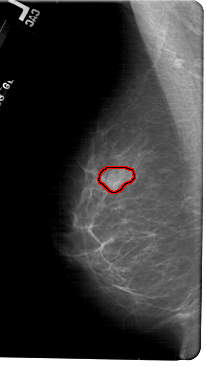

FILE: A_1833_1.LEFT_MLO.OVERLAY

TOTAL_ABNORMALITIES 1

ABNORMALITY 1

LESION_TYPE MASS SHAPE LOBULATED MARGINS OBSCURED

ASSESSMENT 3

SUBTLETY 3

PATHOLOGY BENIGN

TOTAL_OUTLINES 1

BOUNDARY